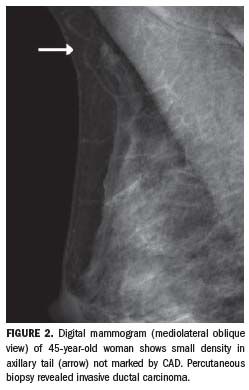

Retrospective studies are, however, biased by the higher prevalence of cancer in study populations compared with the screening setting, and by the incorrect assumption that radiologists always accept prompted suggestions. Contrary to this assumption,1 readers tend to ignore the majority of CAD marks; up to 16% of lesions they detect were missed by the software system (Figure 2).11 It is consequently recommended that radiologists use CAD only after the preliminary reading, and that if CAD fails to mark an area the reader thought was suspicious, the patient should still be recalled.11